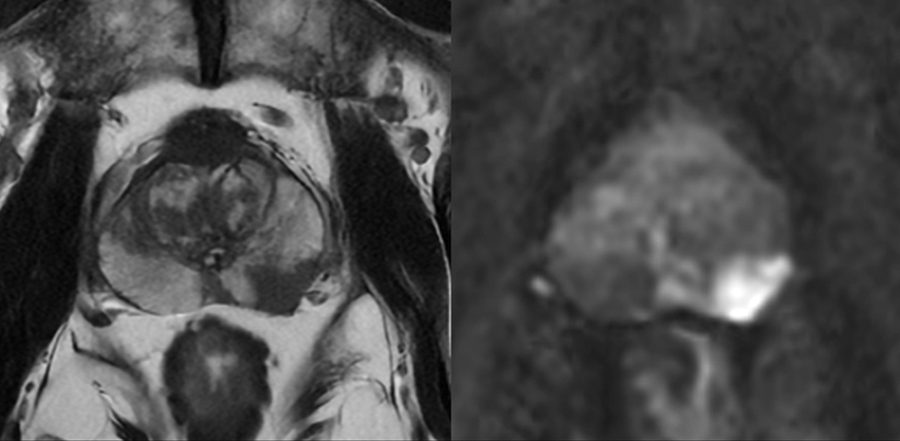

Fortsatt utredning av män med förhöjt PSA-värde sker sedan några år med magnetresonanstomografi (MRT). MRT prostata har snabbt fått stor spridning; 2022 hade 88 procent av männen som diagnostiserades med prostatacancer genomgått MRT före biopsin [1]. MRT utförs numera vanligen med ett kort protokoll utan intravenöst kontrastmedel och tar då ungefär en kvart att genomföra. Röntgenläkaren bedömer sannolikheten för kliniskt betydelsefull cancer enligt PI-RADS (Prostate imaging reporting and data system) på en femgradig skala där 5 motsvarar mycket hög sannolikhet och 1 mycket låg sannolikhet (Figur 1). Trots standardiserad bedömning med PI-RADS förekommer skillnader mellan olika bedömare [2].

Figur 1. MRT-bild av prostata med drygt 1,5 cm stor tumör dorsalt till höger i bild (PI-RADS 5). Biopsier visade kliniskt betydelsefull prostatacancer.